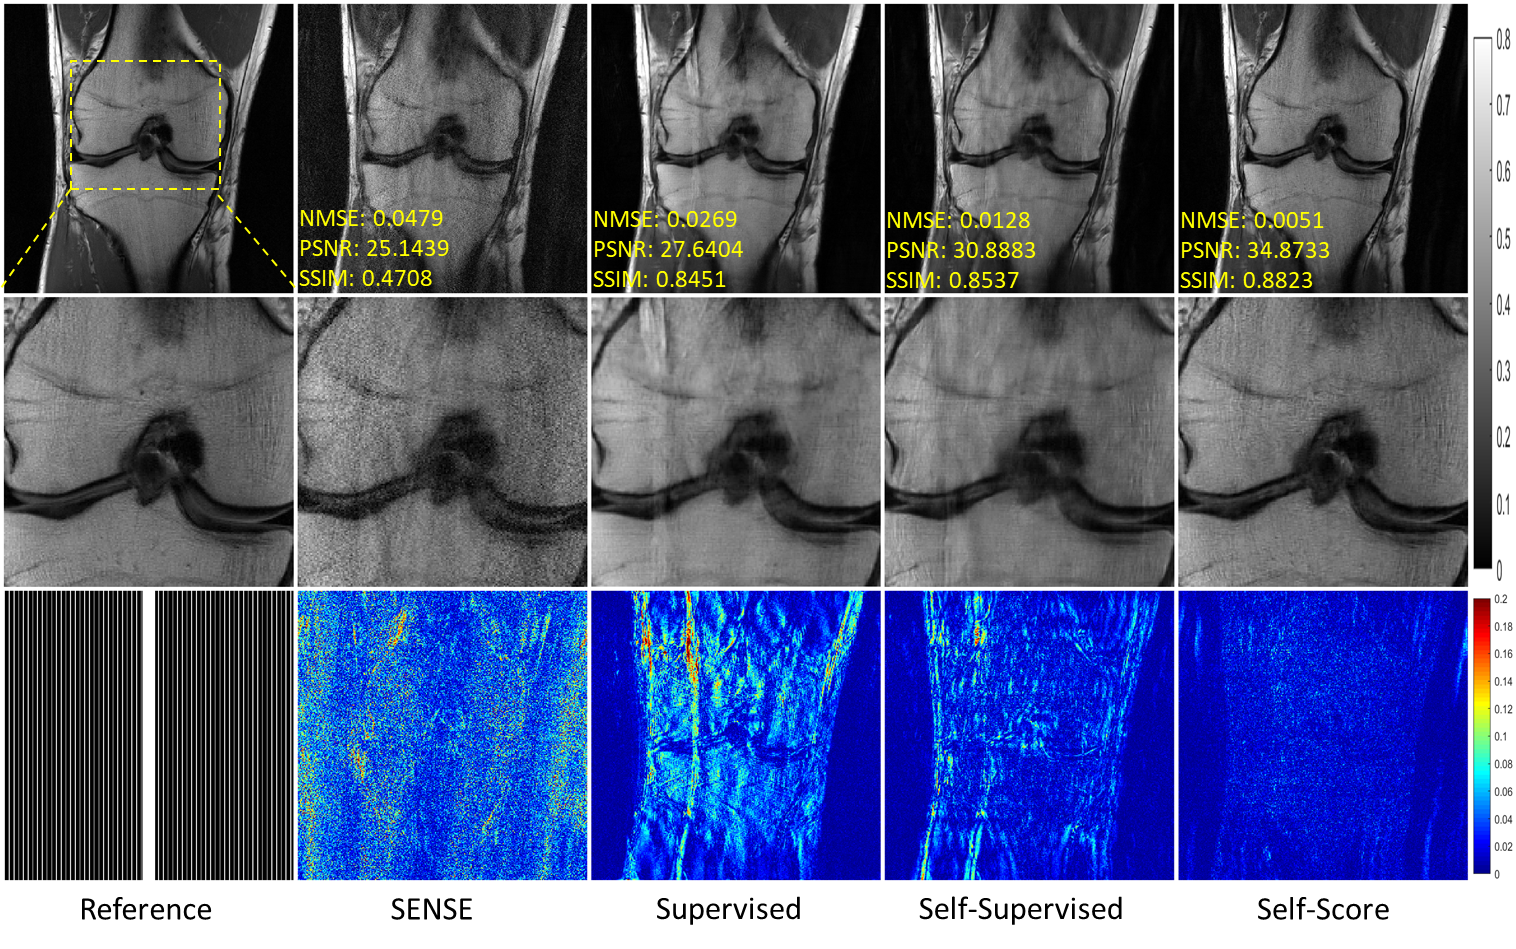

5.2.1 Pattern Shift

In this section, we verified the performance of various methods when the sampling patterns were inconsistent during training and testing. Figure 5 shows the results of various methods trained on a 5-fold randomly sampling pattern and reconstructed on 6-fold uniformly sampled data. Although SENSE is not affected by the pattern shift, it performs poorly because the prior is not sufficiently introduced. The aliasing pattern remains in the reconstruction results of both supervised and self-supervised learning methods. In particular, comparing Figure 4 with Figure 5, we can see that both supervised and self-supervised methods degrade significantly due to the pattern shift. On the other hand, it is easy to see that our proposed method achieves satisfactory performance in both aliasing pattern suppression and detail recovery. The quantitative metrics are shown in Table 2, confirming our method’s superiority.

Refer to caption

Figure 5: Reconstruction results under uniform undersampling at R=6𝑅6R=6. The corresponding models were trained on a randomly sampled pattern at R=5𝑅5R=5. The values in the corner are NMSE/PSNR/SSIM values of each slice. Second and third rows illustrate the enlarged and error views, respectively. The grayscale of the reconstructed images and the color bar of the error images are at the right of the figure.

Table 2: Quantitative comparison for various methods on the fastMRI knee dataset.

The above experiments validate the superior generalization ability of the proposed method in terms of sampling pattern shifts.

5.2.2 Data Shift

In this section, we verified the performance of various methods when the data type (anatomies) were inconsistent during training and testing. Figure 6 shows the results of various methods trained on fastMRI knee data and reconstructed on fastMRI brain. The self-supervised method based on k𝑘k-space interpolation in the paper is no longer applicable due to the different number of channels in the two data sets. Similar to the pattern shift experiment results, SENSE performs poorly, although it is not affected by data shift. The supervised learning method reconstructs the image aliasing pattern residuals, verifying that it also generalizes poorly in data shift. The proposed method in this paper can accurately reconstruct images, thus verifying its superior generalization in data shift.

Figure 6: Reconstruction results of fastMRI brain data under uniform undersampling at R=6𝑅6R=6. The corresponding models were trained on fastMRI knee data. The values in the corner are NMSE/PSNR/SSIM values of each slice. Second and third rows illustrate the enlarged and error views, respectively. The grayscale of the reconstructed images and the color bar of the error images are at the right of the figure.